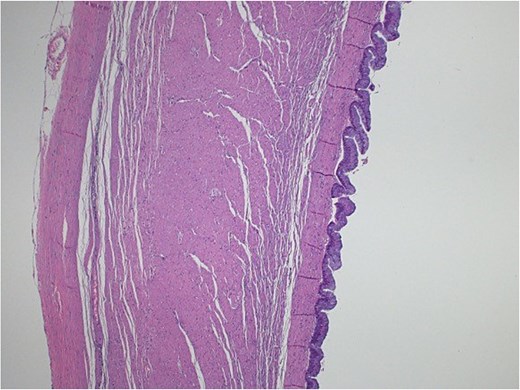

Light microscopy images of the appendix show low-grade dysplastic epithelium on the surface of the appendix (hematoxylin and eosin stain; 10×).

Light microscopy images of the appendix (A, B) show low-grade dysplastic epithelium on the surface of the appendix (hematoxylin and eosin stain; 4×).